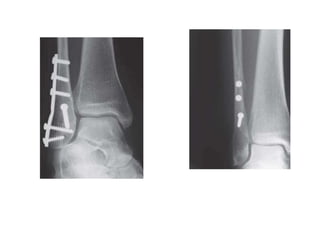

Fixation techniques:

Ankle fracture

Fixation of lateral

malleolus

Simple oblique

fracture

(SER 3,4)

Inter frag screw

+/- neutralization plate

Or

Malleolar screw

Simple transverse

(PER 3,4)

Compression plate

Comminuted fracture

(PAB 3)

Bridge platting

IM nailing

Fixation of medial

Vertical fracture

(SAD 2)

2 transverse screws

Antiglide plate

Oblique fracture

Two 4.5 mm partially

threaded cancellous

screws perpendicular

to the fracture line

Transverse fracture

Tension bend wire

Fixation of

posterior

<25 % of plafond

Can be conserved

>25% of plafond

Cancellous screws

AP or